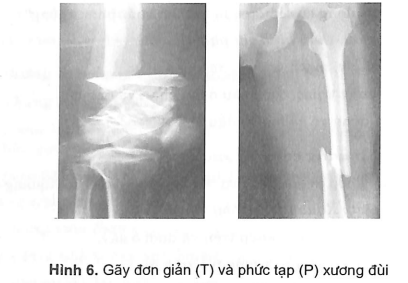

3.7.1. Xương

- Gãy đơn giản: gãy ngang, gãy chéo, gãy xoắn, gãy cành tươi ở trẻ em.

- Gãy phức tạp: gãy nhiều tầng, nhiều đoạn, nhiều mảnh.

- Đọc loại gãy:

- Gãy đơn giản (gãy ngang, gãy chéo xoắn...).

- Gãy phức tạp (gãy nhiều tầng, nhiều mảnh...).